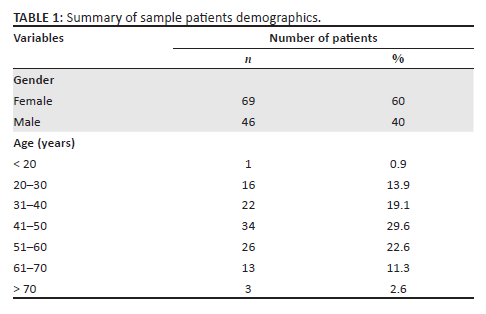

A total of 115 patients were included in this study, aged between 19 and 83 years (mean: 46 years ± 13.3), with the majority in the 41-50 and 51-60-year age groups (Table 1). The female to male ratio was 1.5:1 (Table 1). Digital subtraction angiography detected ruptured aneurysms in 94 of 115 patients. Fourteen of the 94 patients (15%) had multiple aneurysms. Of the 14 patients, 10 patients had one additional aneurysm, three patients had two aneurysms and one patient had three additional aneurysms. In total, DSA detected 113 ruptured and unruptured aneurysms in 94 patients. Therefore, 94 aneurysms per patient-basis and 113 aneurysms per aneurysm-basis were detected by the gold standard (DSA) (Table 2). No identifiable cause of SAH was found in 21 patients (18%).